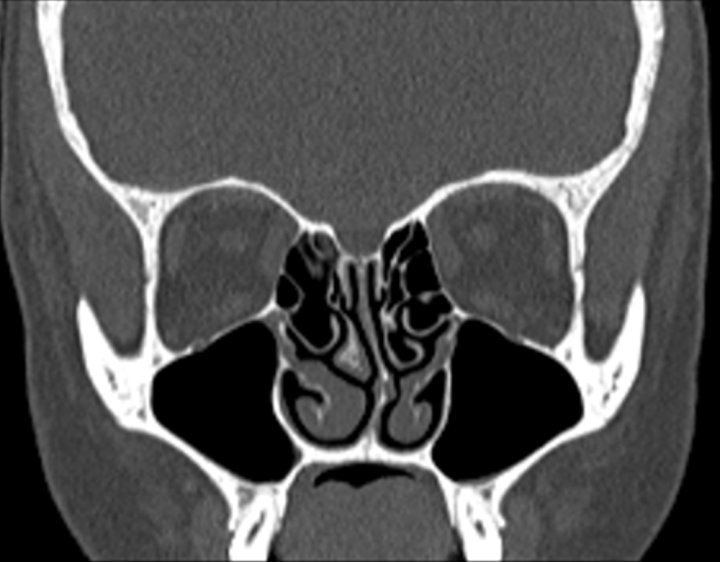

Click any image for labels.